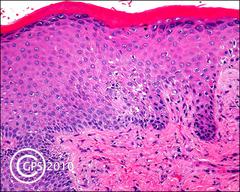

Serous inflammation

Front

Blister